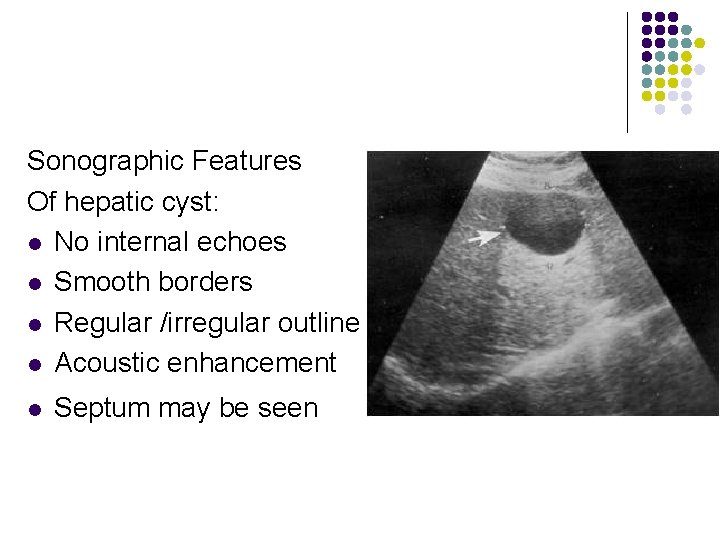

Ultrasound Findings of Cystic Lesions On ultrasound examination the cyst walls are thin , with well-defined borders, and anechoic with distal posterior enhancement.

Sonographic Features Of hepatic cyst: l No internal echoes l Smooth borders l Regular /irregular outline l Acoustic enhancement l Septum may be seen